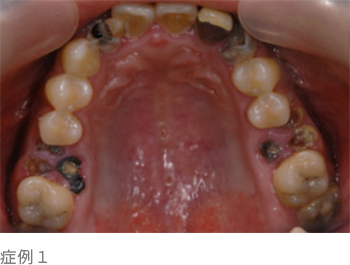

ほとんどの方が大切な歯を失う要因として虫歯を連想されると思いますが、虫歯は宿主、細菌、時間、糖質摂取等の因子が全て揃うと発症し、"歯そのもの"が破壊される病気(写真下)です。

歯周病は細菌性バイオフィルム、宿主生体防御機構の低下、生活習慣、時間などこれら1、2つの因子が揃うだけで発症する"歯を支えている周りの組織(歯周組織)"に起こる病気で、虫歯と同等以上に歯周病(歯槽膿漏)で歯を失ってしまう方が多いのです。